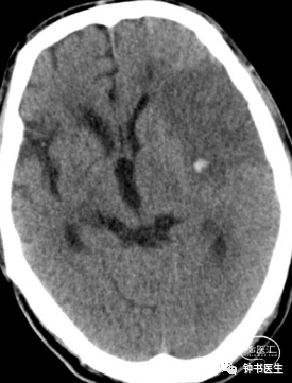

2012-11-8 CT

左颞部脑梗加重,出血渗出点增多。继续加强镇静镇痛治疗。

2012-11-10 CT

病情趋稳定,转出监护室治疗。